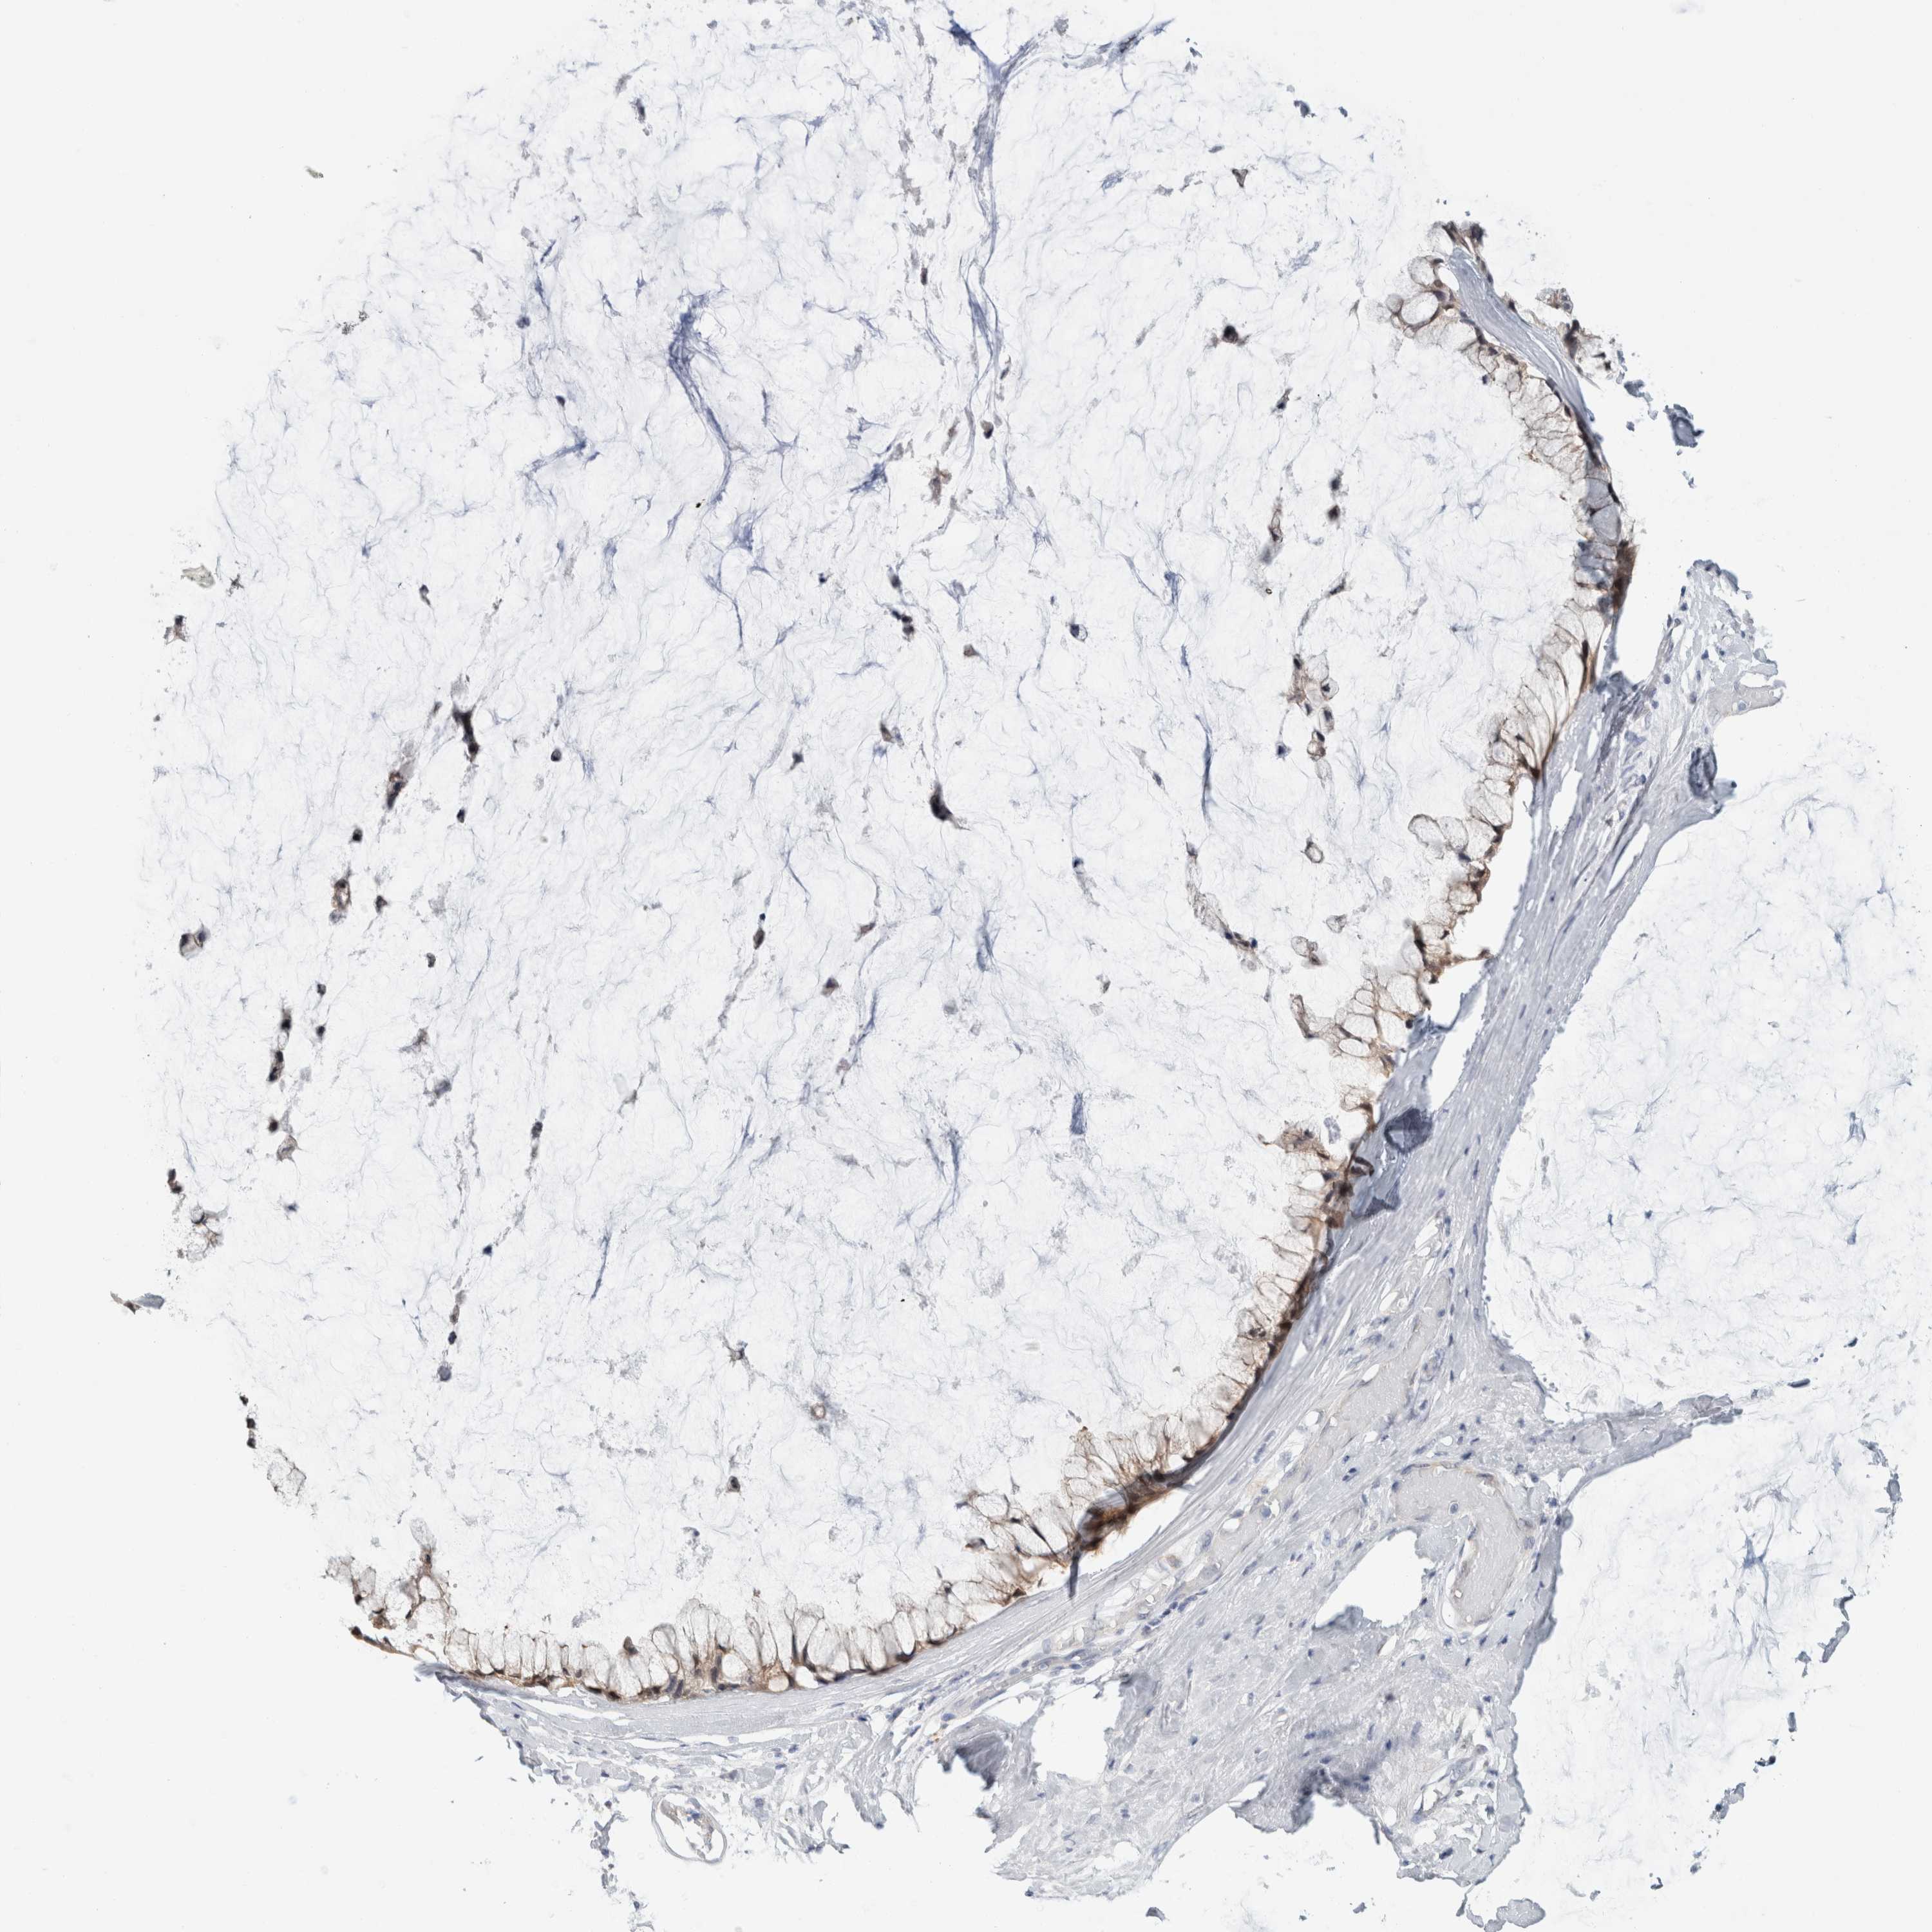

OVARIAN CANCER - Protein expressioni

A mouse-over function shows sample information and annotation data. Click on an image to view it in a full screen mode. Samples can be filtered based on level of antibody staining by selecting one or several of the following categories: high, medium, low and not detected. The assay and annotation is described here.

Note that samples used for immunohistochemistry by the Human Protein Atlas do not correspond to samples in the TCGA dataset.

Antibody stainingi

Antibody staining in the annotated cell types in the current human tissue is reported as not detected, low, medium, or high, based on conventional immunohistochemistry profiling in selected tissues. This score is based on the combination of the staining intensity and fraction of stained cells.

Each image is clickable and will lead to virtual microscopy that enables deeper exploration of all samples and also displays staining intensity scores, fraction scores and subcellular localization as well as patient and tissue information for each sample.

Antibody HPA011337

Cystadenocarcinoma, mucinous, NOS

Cystadenocarcinoma, serous, NOS